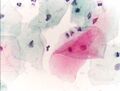

صورة مجهرية لاختبار عنق الرحم تظهر داء المشعرات . كائن المشعرات يظهر في أعلى اليمين. صبغة عنق الرحم .